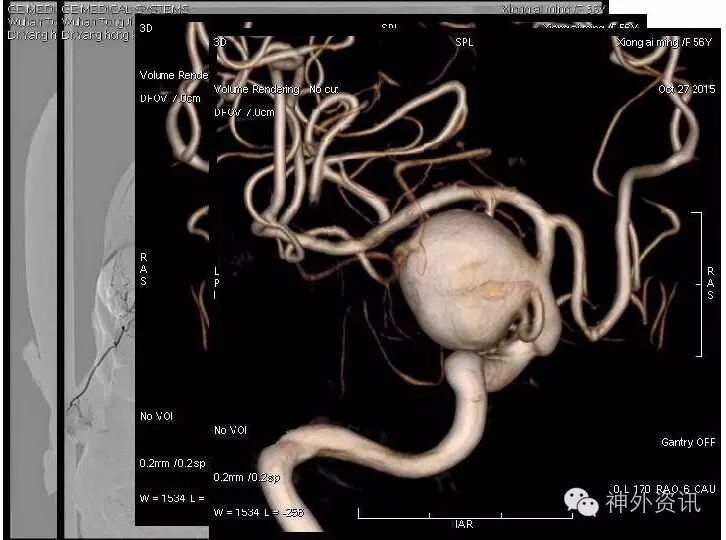

《后交通大动脉瘤》